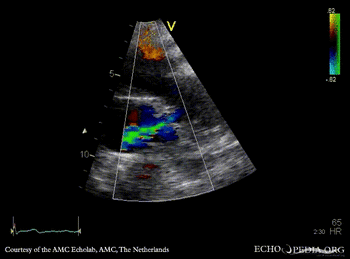

Open ductus Botalli

Suprasternal view Suprasternal view with Color Doppler, open ductus Botalli